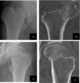

Malunited fracture of femoral neck

Coxa vara